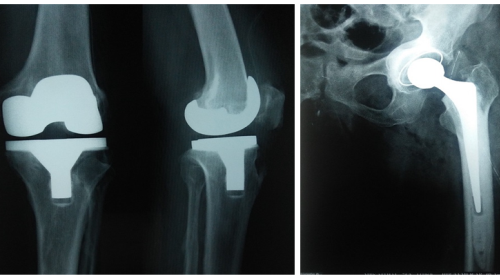

Other than the treatment for fractures he introduced spinal injury management in our region. He has done many knee joint and hip joint replacements. Because of that many old age arthritic patients are walking around without pain.

➤ Joint replacement

Human knee joints are strong. They help in standing, walking, sitting, squatting, crosslegged sitting, jumping and swimming. They are very useful for all kinds of human body moments. But when they bear a lot of weight and work too much of time they start degenerating. Initially, the soft tissues in between the bones of a joint Which are known as meniscus start degenerating.